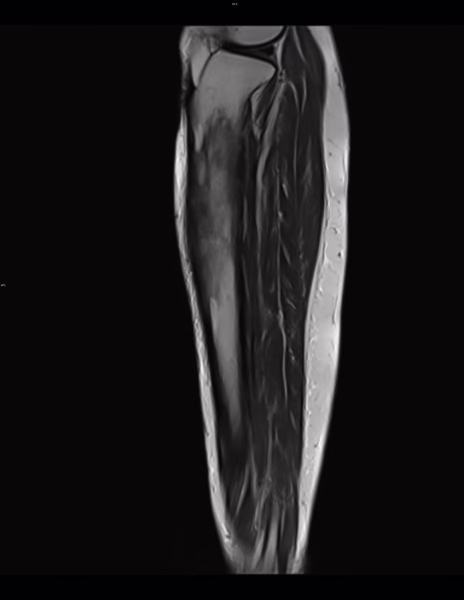

rnm

Se realizaron cortes sagitales, axiales y coronales con técnica de espín eco con el protocolo habitual.

Se identifican edema en el tejido celular subcutáneo adyacente a la tibia y grupos musculares en la región anterior y medial de la pierna.

Existen cambios en la morfología e intensidad del hueso esponjoso de la tibia que involucra la diáfisis proximal y tercio medio con áreas de baja intensidad en el hueso esponjoso medular así como de mayor intensidad, la cortical al parecer se encuentra conservada.

La intensidad de las estructuras musculares se encuentra conservada.

IMPRESION DIAGNOSTICA:

Edema en el tejido celular subcutáneo adyacente a la tibia y grupos musculares en la región anterior y medial de la pierna.

Existen cambios en la morfología e intensidad del hueso esponjoso de la tibia que involucra la diáfisis proximal y tercio medio con áreas de baja intensidad en el hueso esponjoso medular así como de mayor intensidad, la cortical al parecer se encuentra conservada, cambios de proceso infiltrativo óseo de etiología a determinar.